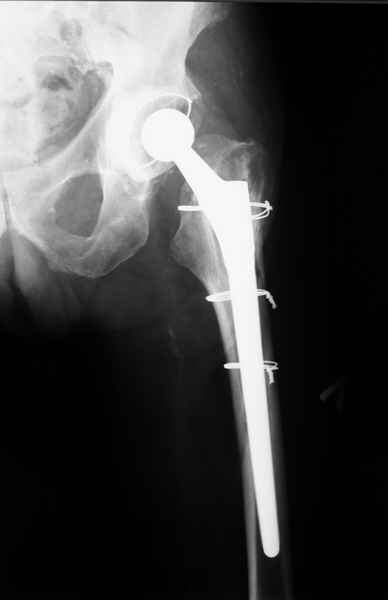

2. Применение ножки дистальной фиксации, мы отдаем предпочтение ножке Вагнера с фиксацией проксимального отдела на ножке. Более травматичное вмешательство, но при стабильной фиксации ножки реабилитация идет в обычном режиме.

Хочется показать два подобных случая, П-ка З. 72 лет и п-т Г. 80 лет. Сразу принимаю замечание, что это были ножки цементной фиксации, просто под руками не было бесцементника.